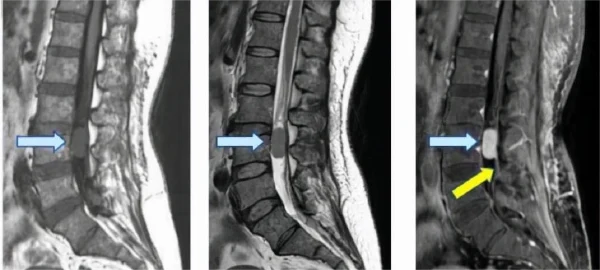

在这份全面的医学检查报告中,患者主要表现为双下肢麻木伴无力,经过多项检查最终确诊为胸椎椎管肿瘤。报告提及的主要异常包括胸椎椎管内占位,腰椎退行性改变及椎间盘膨出。正常参考范围应为无椎管内占位,无明显腰椎退行性改变及椎间盘无异常膨出。

椎管肿瘤是一种位于脊髓或脊髓周围椎管内的肿瘤,可以是原发性的,也可以是从其他部位转移来的。报告中显示的“胸椎椎管内占位”提示这一部位存在异常组织增生,可能是良性或恶性的肿瘤。此外,腰椎退行性改变和椎间盘膨出,虽然在本例中未被重点讨论,但也可能会成为病情进一步发展的隐患。

椎管肿瘤可对中枢神经系统和脊柱造成严重损害,主要症状包括持续性疼痛、感觉异常(如麻木)、肢体无力、甚至瘫痪。如果肿瘤位于胸椎及其周围,较严重的病例还可能影响内脏功能,例如大小便失控、呼吸困难等。

一个全面的综述指出,椎管肿瘤属于神经系统较难察觉的病变,如果不及时干预,肿瘤会慢慢增大,压迫脊髓或神经根,导致不可逆的神经损伤。相关研究表明,约50%的原发性椎管内肿瘤为良性,虽然一般增长缓慢,但同样不能忽视其潜在威胁。